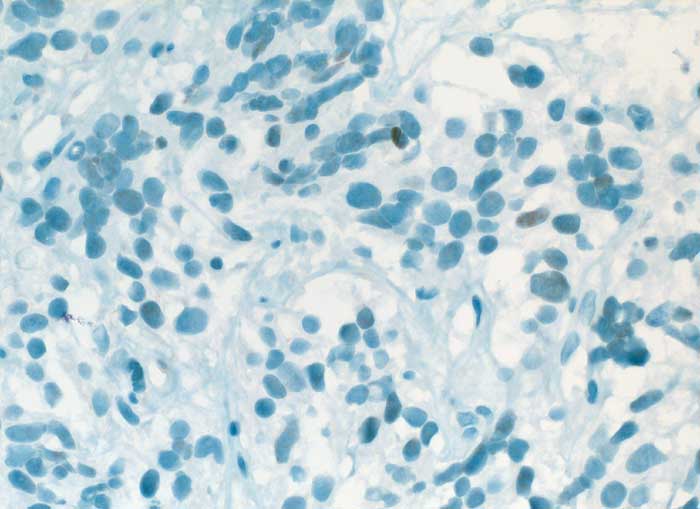

Karzinoid

benigner Tumor

Lunge

Die spindeligen Tumorzellkerne sind fokal schwach positiv für TTF1

Histologie

Immunhistochemie

TTF-1

400